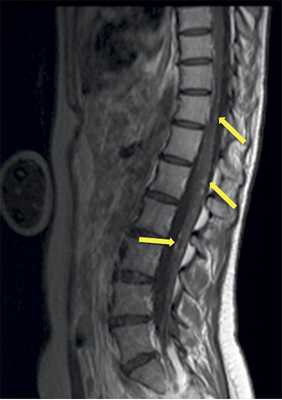

Учитывая темп развития симптомов, был заподозрен злокачественный характер опухоли. В день поступления (02.03.16) пациентке выполнена МРТ головного мозга и спинного мозга с контрастным усилением. Была выявлена диссеминация процесса с появлением опухоли в левом внутреннем слуховом проходе, множественных очагов патологического накопления контрастного вещества оболочек спинного мозга. Динамика распространения первичного очага и метастазирование представлены на рис. 1 и 2.

Рис 2. МРТ от 02.03.2016 - метастазирование опухоли по оболочкам спинного мозга (указаны стрелками).